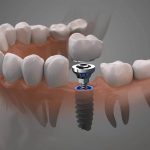

Same Day Dental Implants in Houston TX

If you’re looking to improve your quality of life and replace your missing teeth with the help of dental implants! At VIP Dental Implants, we focus exclusively on using dental implants for replacing your missing teeth. Call us for a free consultation at (832) 224-2615 or visit us at VIP Dental Implants in Houston, TX.